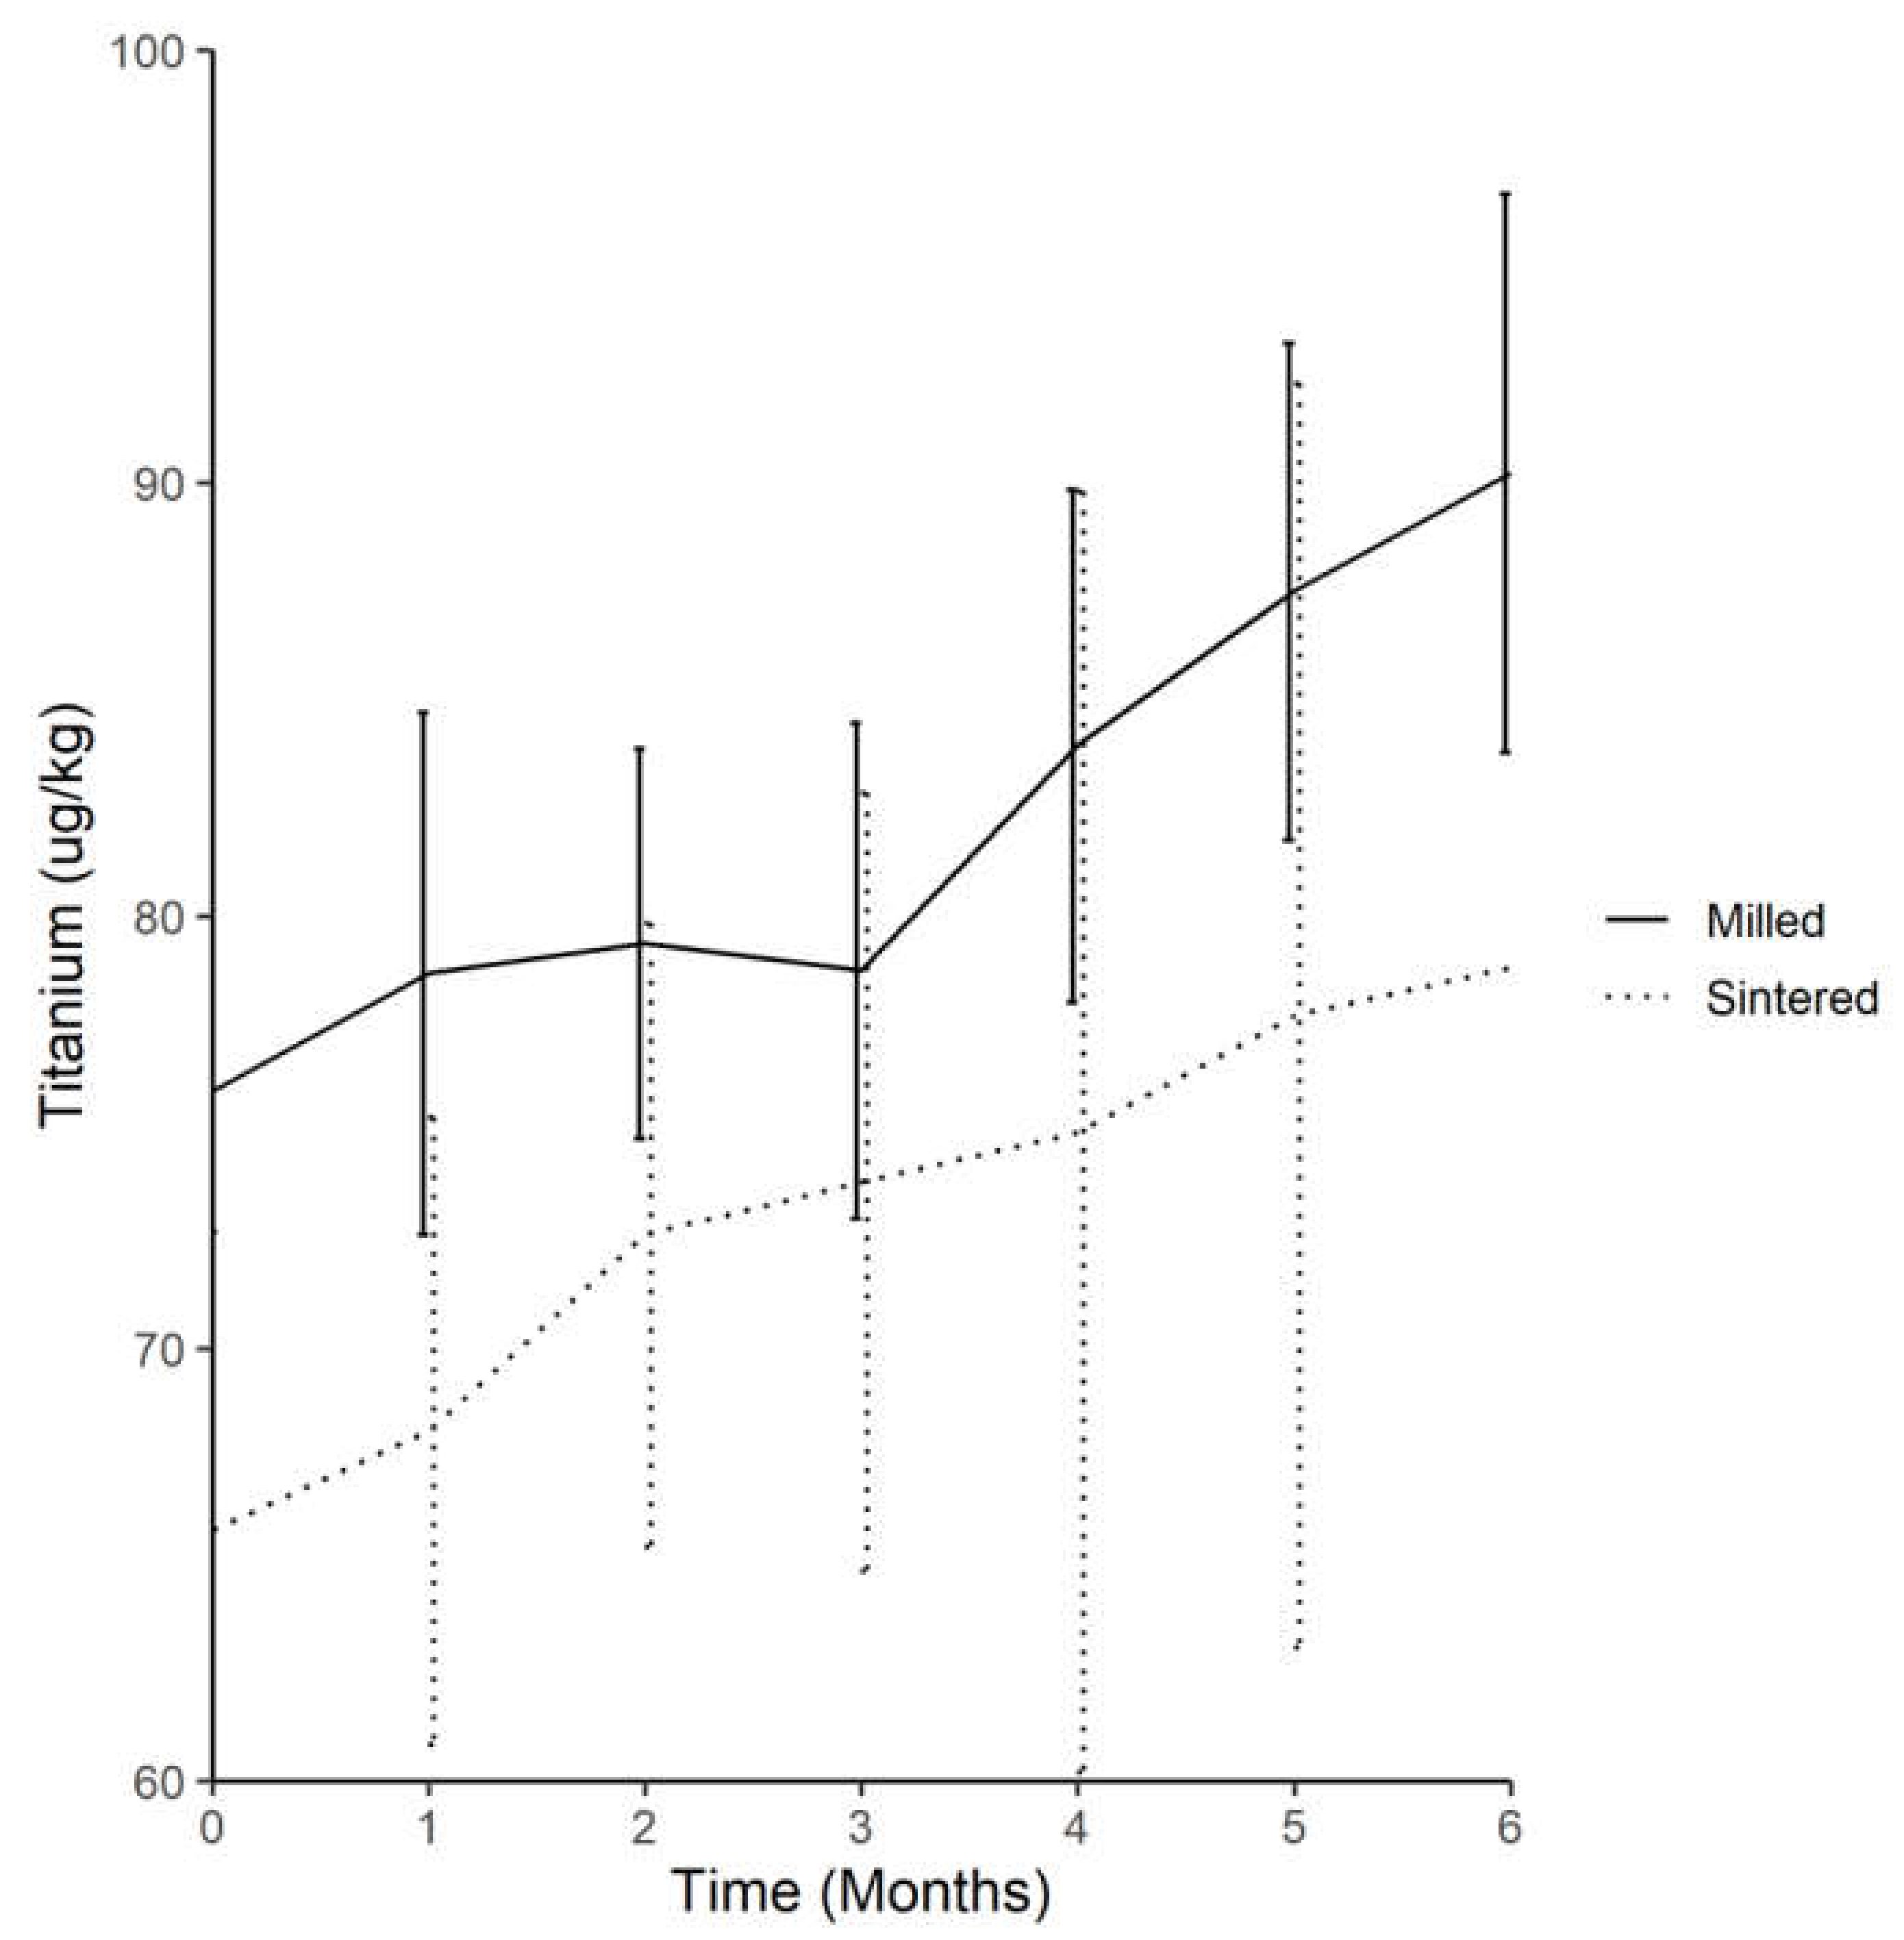

2.1. Analysis of Titanium Concentration in Serum

2.1.2. Trend of Serum-Titanium Levels in Test Group 1 (Milled-Titanium Implant) throughout the 6 Month Experimental Period

2.1.3. Trend of Serum-Titanium Levels in Test Group 2 (DMLS-Titanium Implant) throughout the 6 Month Experimental Period

2.1.4. Comparison of Average Serum-Titanium in Test Group 1 (Milled-Titanium Implant) and Test Group 2 (DMLS-Titanium Implant) throughout the Experiment